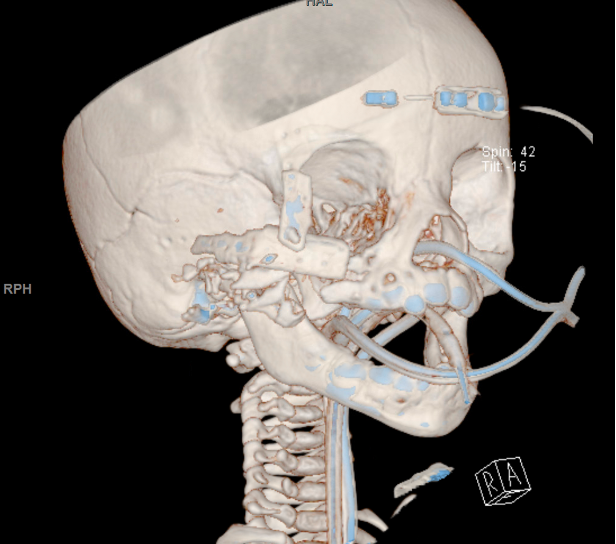

Methods: Here, we present the case of an 8-month-old female who sustained a gunshot wound to the right face resulting in obliteration of her right zygoma and extensive damage to her right lateral orbital wall and infraorbital rim. She underwent enucleation of her right orbit. She was subsequently reconstructed using a MTF biologics cadaveric rib allograft, secured with resorbable plates and screws to restore the structural components of the zygoma, infraorbital rim, and lateral orbital wall.

Results: The surgical approach aimed to restore facial symmetry, maintain orbital integrity, and allow for future facial growth without compromising function. A virtual planning session preoperatively allowed accurate measurement of the patient’s defect and fabrication of both a defect model and perfected model using a mirror image of the patient’s unaffected side. Postoperatively, the patient exhibited stable structural support in the orbitozygomatic region with satisfactory aesthetic outcomes. Early follow-up demonstrated adequate healing with no signs of graft rejection or infection. Long-term follow-up will be necessary to monitor facial growth and ensure ongoing stable functional and aesthetic results.

Outcomes: Intraoperative CT scan was taken demonstrating satisfactory position of cadaveric rib segments resulting in re-establishment of the architecture of the zygoma and orbital rims. Early postoperative follow-up demonstrated adequate healing and establishment of zygomatic projection with no signs of graft rejection or infection.

Preoperative CT 3D Reconstruction